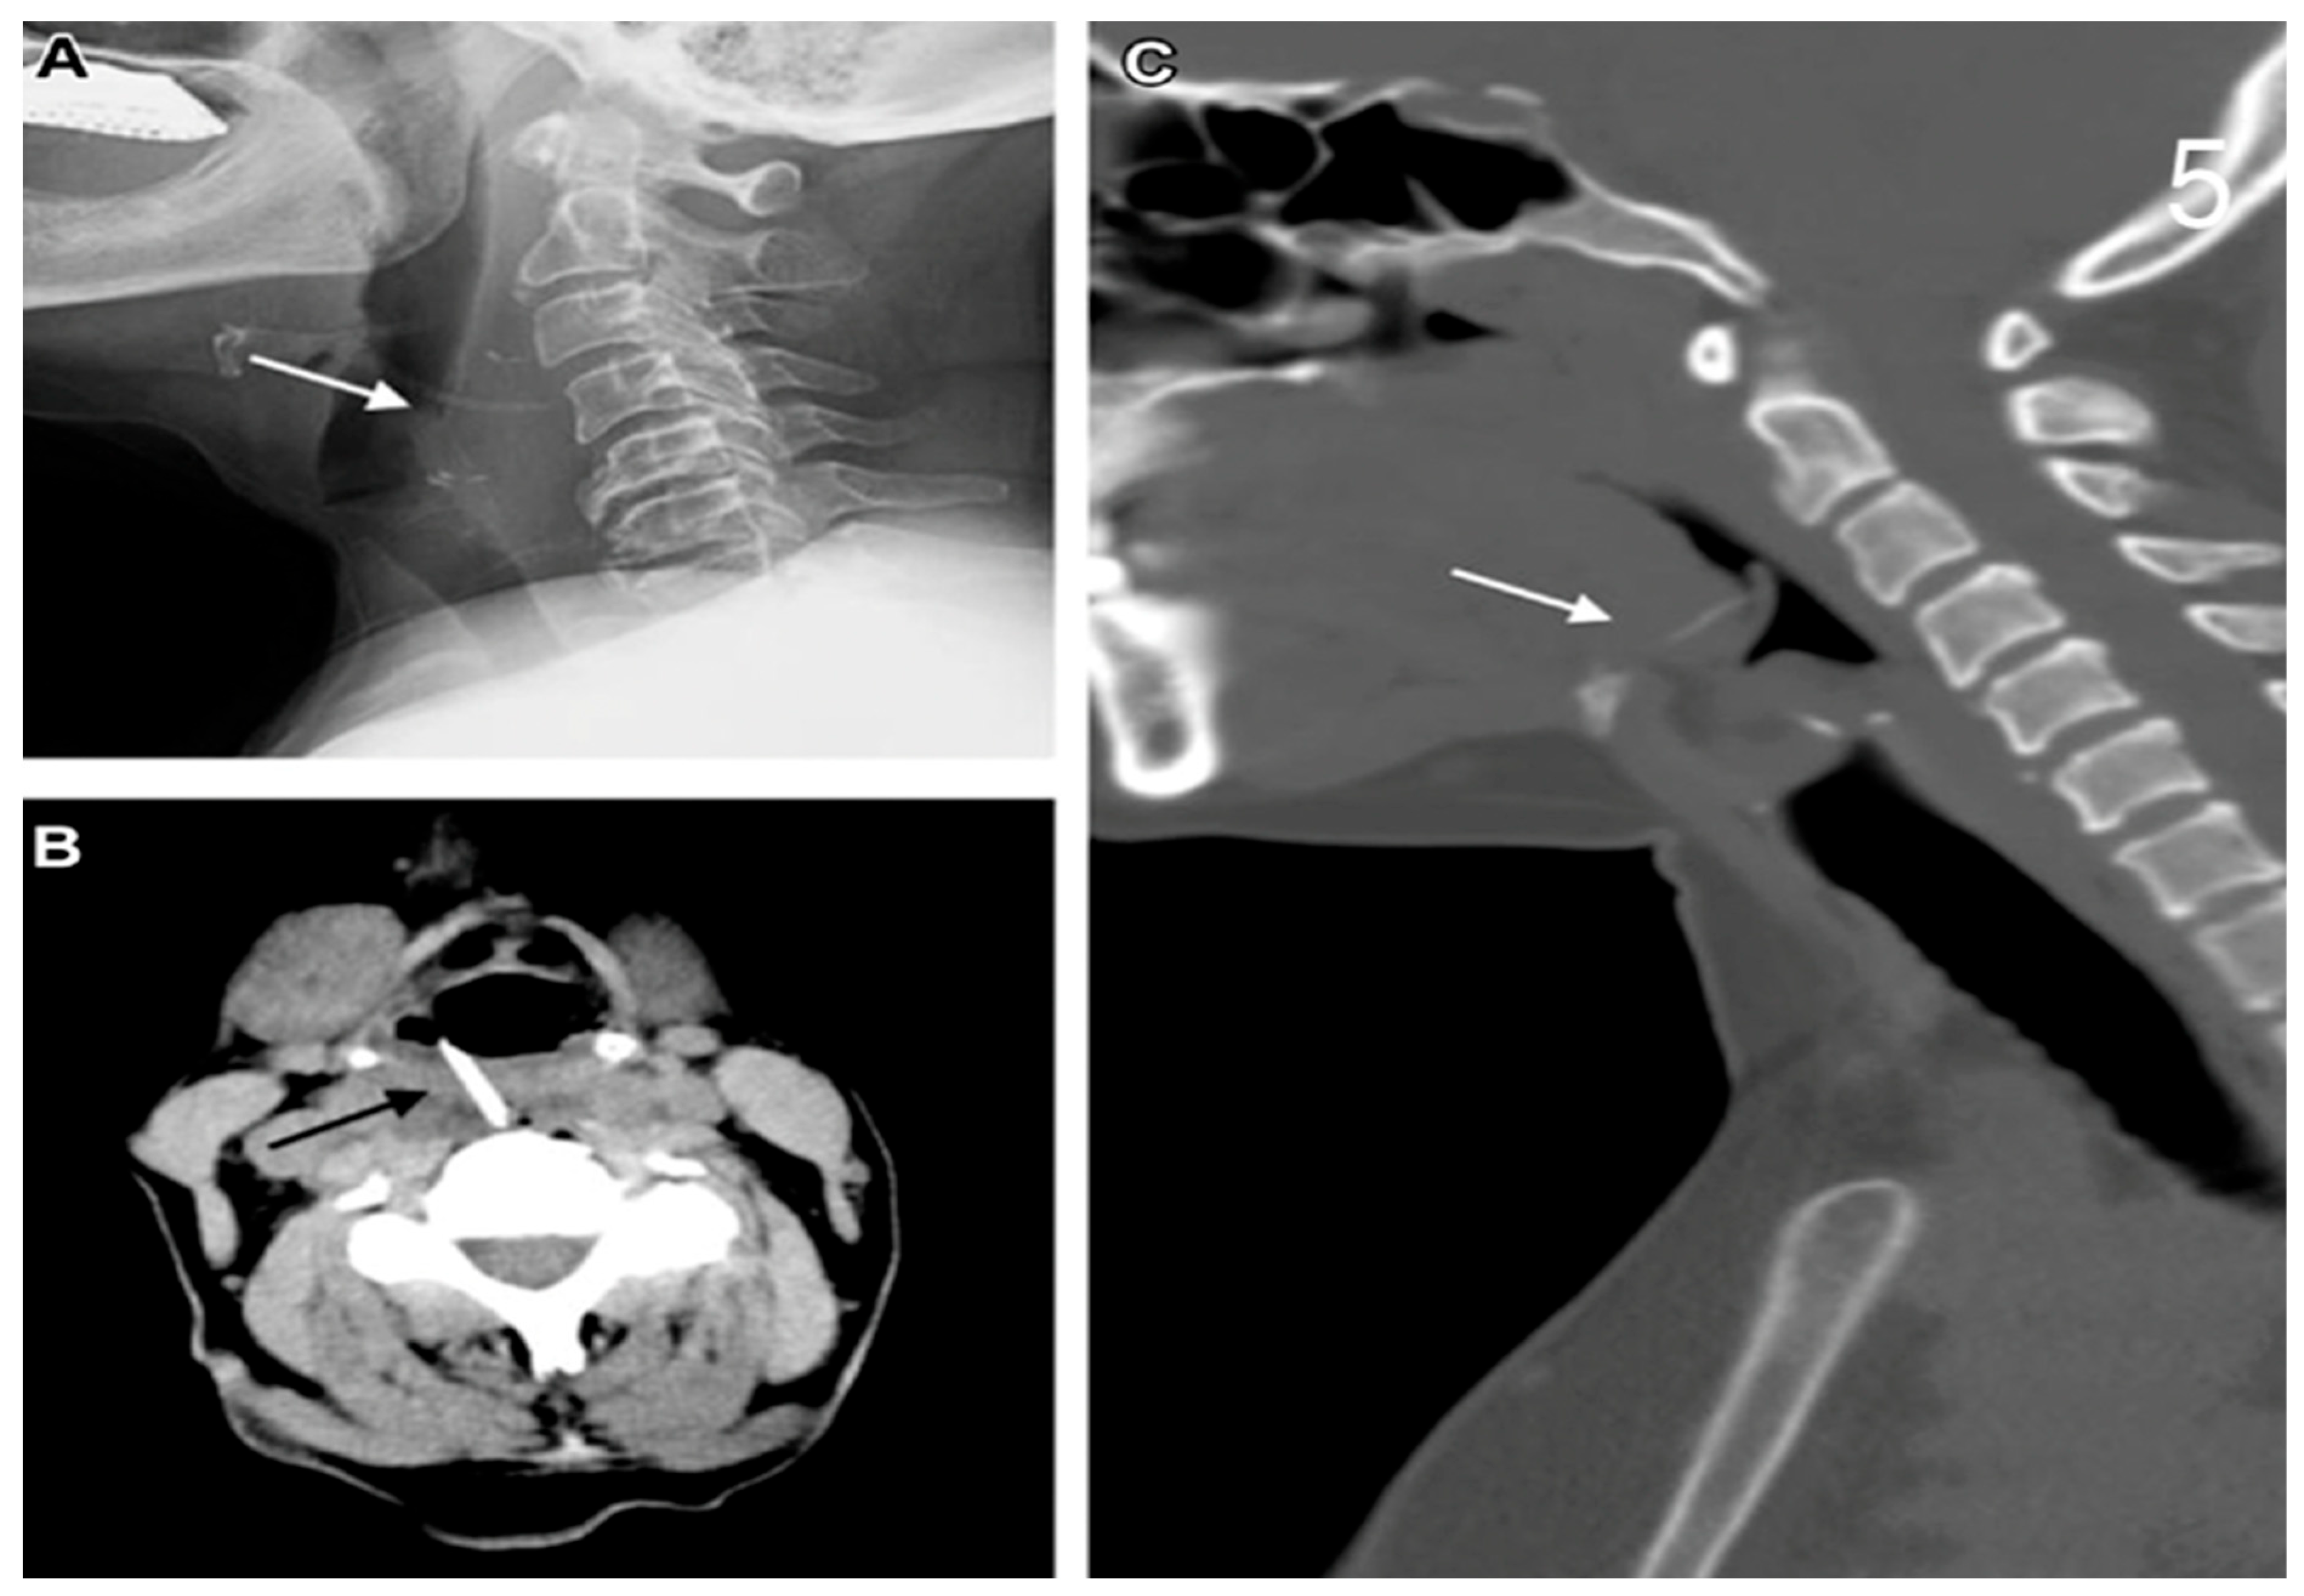

2.2. Diagnosis and Symptoms